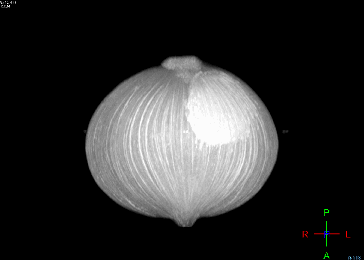

这款静音型 MR 3.0T核磁共振构建了全新的磁共振平台,配有全套相控阵线圈和丰富的软件,能进行全身各部位的MRI检查,尤其是在神经系统、骨关节和肌肉、腹部、血管、乳腺、子宫附件、前列腺、全身肿瘤筛查方面具有明显优势。比如在血流发生改变时就能向脑缺血高危人群预警,在肿瘤没形成前提醒你哪个部位有发生肿瘤倾向,对已经出现的小至2毫米的微小病灶可以清晰辨别,从而实现早期诊断。同时,该台3.0T磁共振在具备高分辨率的同时,没有电离辐射,对人体安全无害,特别是对儿童的危害降至最低。另外,该设备配备了高清晰快速扫描技术,在图像清晰程度增加的前提下,检查时间大大缩短,不需搬动患者,仅需要6分钟即可完成全身检查。